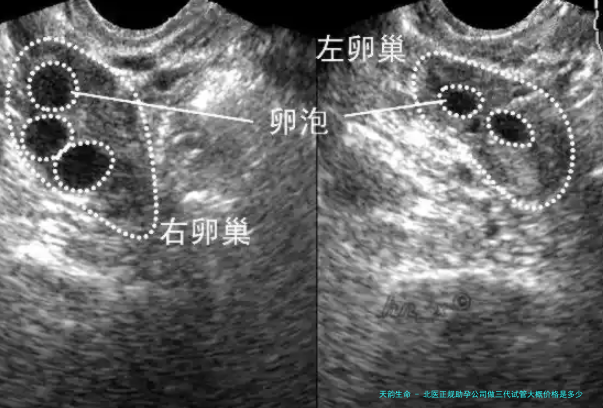

二、促排卵撤排卵费用:费用差距的关键取决于用药种类、用用药量等。服用卵的费用差距主要是因为食用卵时的掌握技术,也分为麻木和非麻木费用。这部分费用大概在一万到两万元。